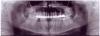

Pasha Опубликовано 12 августа, 2011 Поделиться Опубликовано 12 августа, 2011 (изменено) Добрый день!Два с половиной года назад мне поставили на передние зубы металлокерамические коронки (3 моста по 4 зуба каждый), спустя какое то время выяснилось, что "тройку" левую плохо депульпировали и там образовалась гранулема. Два года назад мне сделали резекцию верхушки, и все это время ничего не беспокоило. Но позавчера вдруг резко начало побаливать. Сама денса когда на нее давлю не болит, зуб как то тоже странно болит, болит болит, потом вдруг резко перестает на какое то время, потом все опять. Иногда появляется чувство тяжести в этом зубе, когда на нем жую, то вроде как давит, потом и это чувство проходит. Сходил, сделал снимки, хирург говорит, что они хорошие, судя по ним никакого воспаления нет. На всякий случай прописала цифран СТ и содовые ванночки. Посмотрите, пожалуйста, на снимки.... как считаете, действительно нет воспаление? И почему может болеть зуб... В итоге не хотелось бы его потерять, он ведь опорный А вообще, если вдруг придется в один прекрасный день все менять, то что бы вы посоветовали? включая импланты и т.д. Заранее спасибо! Изменено 12 августа, 2011 пользователем Pasha Ссылка на комментарий